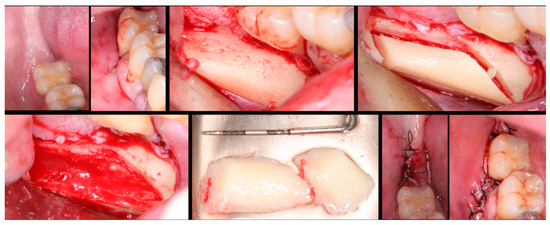

The surgical process, performed by the same surgeon, involved local anesthesia followed by incisions, flap detachment, osteotomy, and membrane elevation. Autologous bone from the mandibular branch (Figure 1) or the mental symphysis (Figure 2), or a porcine xenograft (Figure 3) were used as the graft materials for sinus augmentation. The protocol for this study involved using either two or three syringes of Oteobiol MP3, delivering a volume of approximately 2 to 3 cc per sinus. The contralateral sinus received a similar amount of autologous bone, either from the mental region (desmal with probably some bone of enchondral origin) or the mandibular ramus (desmal origin). Figure 3 and Figure 4 depict one example from each side of maxillary sinus augmentation treatment. Post surgery, the patients followed a prescribed protocol. After six months, a follow-up CT scan was conducted, and dental implants were placed. The final phase involved inserting healing abutments or prostheses, ensuring that no tooth–implant connections were established [20].

Figure 2. Surgical steps for harvesting autologous bone graft from the mental symphysis. In the first row, left to right: anterior mandibular overview, incision and flap detachment, graft drilling. In the second row, left to right: graft removal, chin filling, and sutures.